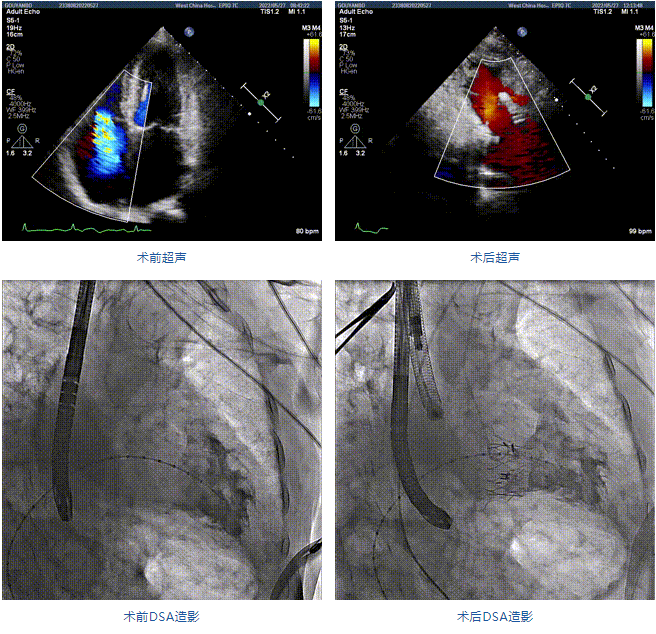

89歲男性。術(shù)前超聲報(bào)告顯示:雙房增大,左室壁肥厚,主、肺動(dòng)脈增寬,三尖瓣重度反流。

團(tuán)隊(duì)前期經(jīng)過(guò)多次討論,制定了周密的手術(shù)策略和預(yù)案。由于患者已是近九旬的超高齡老人,傳統(tǒng)外科開(kāi)胸手術(shù)風(fēng)險(xiǎn)極高,純介入經(jīng)血管三尖瓣替換能夠明顯減少創(chuàng)傷。術(shù)中陳茂及馮沅教授結(jié)合體表定位在造影指示下精準(zhǔn)穿刺右側(cè)頸靜脈并預(yù)置兩把血管縫合器。成功建立經(jīng)皮血管入路后在食道超聲和DSA的引導(dǎo)下順利完成人工瓣膜植入,術(shù)后超聲和造影顯示人工三尖瓣同軸性良好,瓣架固定牢靠,無(wú)反流和瓣周漏,平均跨瓣壓差降為1mmHg。術(shù)畢收緊預(yù)置的血管縫合器縫線完成止血,縫合效果滿意,在手術(shù)室即刻拔除氣管插管。